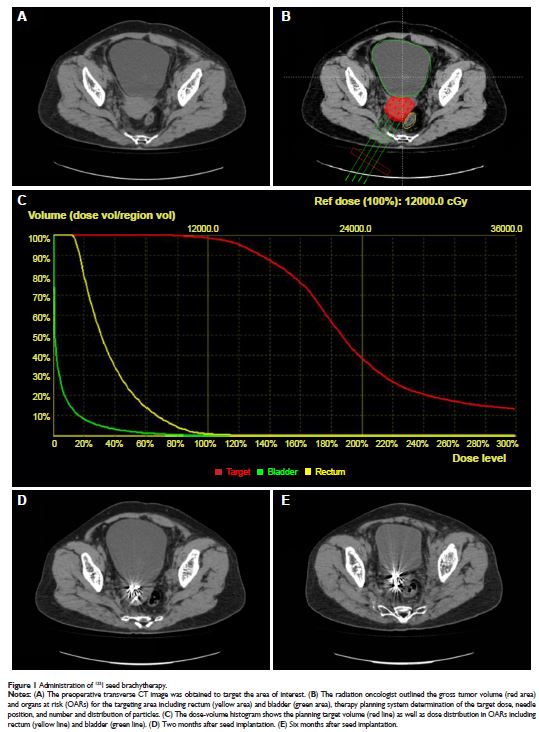

Case Series

- 作者:Wenlong Zhong, Rongcheng Lin, Lei Zhang, Chengyue Jin, Xuesong Li, Qun He, Kan Gong, Zhisong He, Liqun Zhou

- 期刊:OncoTargets and Therapy